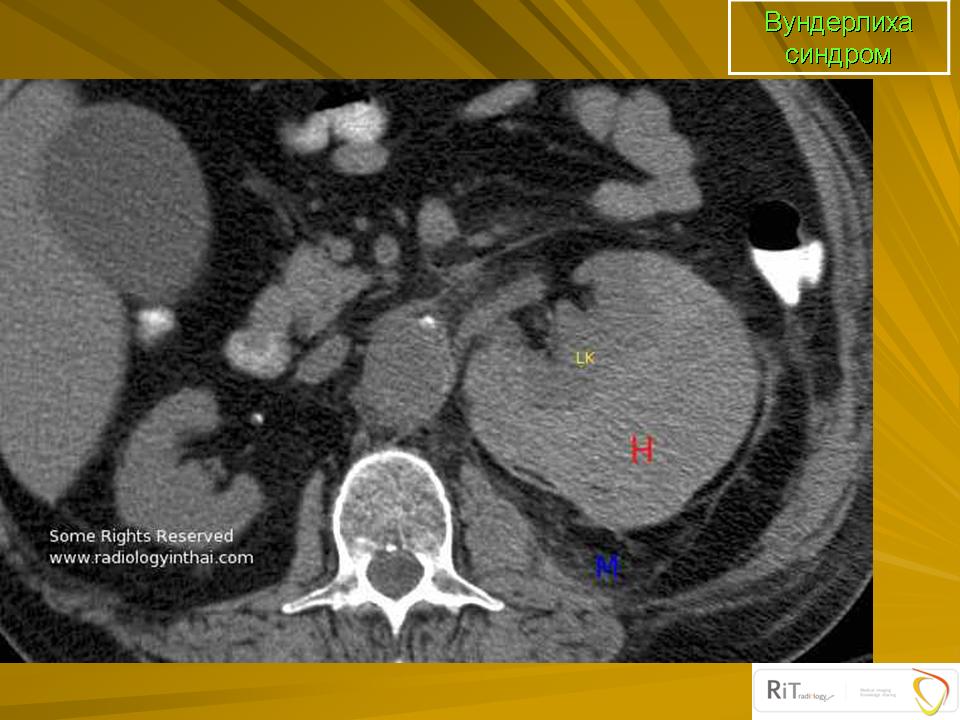

Вундерлих синдром - ndash; спонтанной, нетравматических почечной кровотечение ограничивается субкапсулярной и паранефральный пространстве. Это может быть первым проявлением почечной angiomyolipoma.

Синдром Вундерлиха. В русскоязычной литературе описывается как периренальная гематома, возникающая в результате сотрясения тела или удара в область почек (иначе говоря, травматического генеза). В англоязычной литературе описывается как нетравматическое кровоизлияние в подкапсульное или околопочечное пространство, часто как дебют ангиомиолипомы.